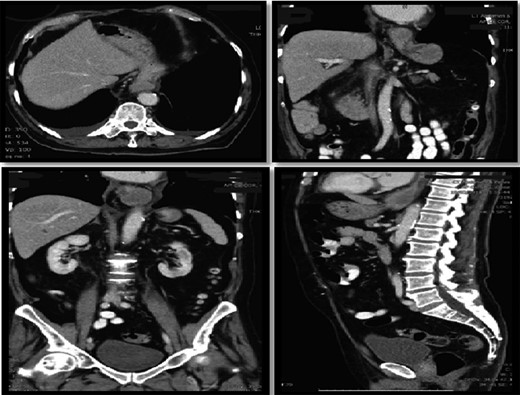

Interval gastroscopy in 2 weeks showed healing mucosal ischemia with slough from 27–30 cm (Fig. 3). Clear fluids were commenced and gradually upgraded to normal diet. Follow-up CT showed no contrast extravasation within posterior mediastinum (Fig. 4) and gastroscopy in 8 weeks showed healed esophagus.

CT scan at 2 weeks showing no contrast extravasation in posterior mediastinum.